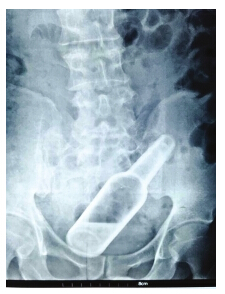

- 男子欠债没还 追债人恼怒将玻璃瓶塞入其肛门(图)

- 时间:2015-09-02 16:26:03